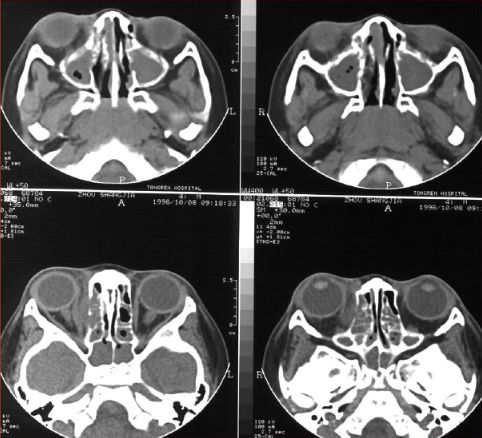

蝶窦炎—眶尖综合症

鼻窦炎—眶尖综合症